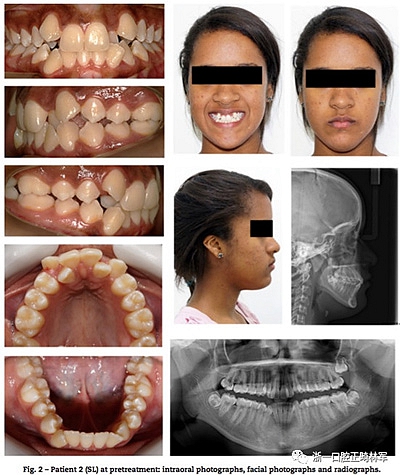

一、患者信息

13歲雙胞胎女性患者,安氏II類錯合畸形伴嚴重上頜牙列擁擠,異位尖牙。臨床檢查提示雙胞胎患者情況類似,如:側貌、長面型、中等頰廊及唇肌松弛。不同點有:一名表現(xiàn)為露齦笑,右上頜側切牙空間不同(圖1,2),頭影測量指標見表1。